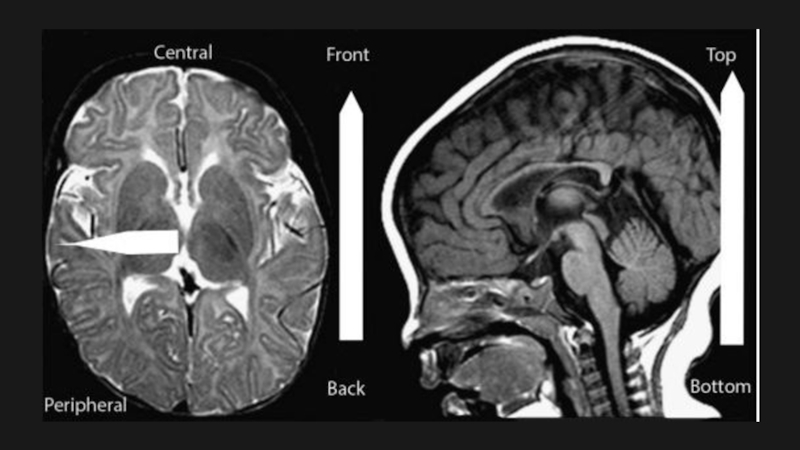

Слайд 28Дисгенезии мозолистого тела

Визуализация:

Отсутствие мозолистого тела на саггитальных, корональных

срезах

На месте отсутствующего мозолистого тела тракты вместо перекреста образуют пучки

Пробста(DTI)

Боковые желудочки разделены и параллельны

Преддверие/затылочный рог бокового желудочка часто расширены

(кольпоцефалия)

Спектр врожденных структурных аномалий МТ

-тотальная агенезия

-частичная агенезия

-гипоплазия

-гиперплазия

Дисгенезии мозолистого тела Визуализация: Отсутствие мозолистого тела на саггитальных, корональных срезахНа месте отсутствующего мозолистого тела тракты вместо